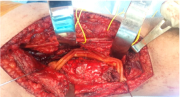

| 13:30, 14 באוגוסט 2023 | משתל טיטניום2.png (קובץ) |  |

425 קילו־בייטים | Motyk | 1 | |

| 13:26, 14 באוגוסט 2023 | משתל טיטניום1.png (קובץ) |  |

1.28 מגה־בייטים | Motyk | 1 | |